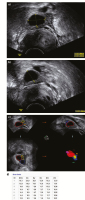

Abbildung 1a-d: Derselbe Follikel mit verschiedenen Presets: (a) Im Preset „Penetration“ wirkt der Inhalt etwas diffus, (b) im Preset „Ovary“ zeigt sich eine klare Kontur, die (c) wiederum einen markanten Follikel im Sono-AVC ergibt. (d) Der Durchmesser beträgt knapp 14 mm, das Volumen 1,4 ml.

Abbildung 2a-d: Befund bei polyzystischen Ovarien: (a) Zunächst werden 2 Follikel mit möglichst klar erkennbaren Konturen gemessen. (b) Bei der Aufnahme des Sono-AVC bleibt man mit den Augen genau am Monitor und bekommt so einen Eindruck der Ausdehnung des Ovars und der Anzahl der Follikel. (c) Mit der den Schirm füllenden Darstellung aller Follikel bekommt man ein eindrucksvolles buntes Bild. (d) Das System kann unbegrenzt viele flüssigkeitsgefüllte Strukturen messen.